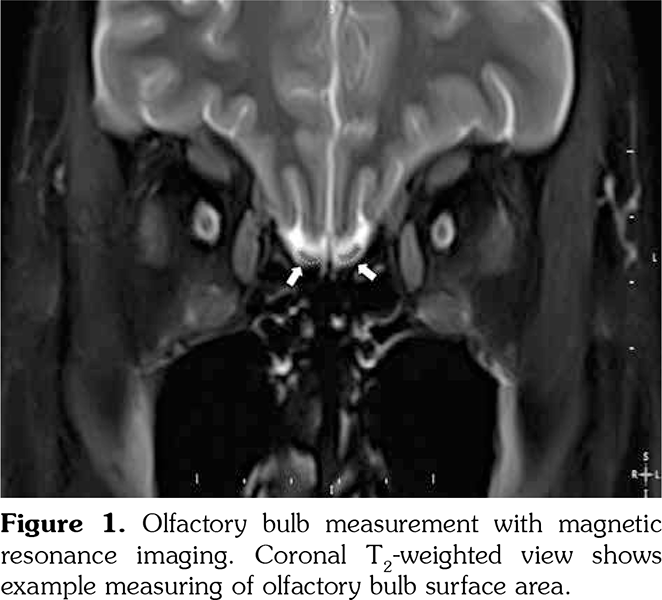

Olfactory bulb volumes were measured using cranial MRI examinations. Total OB volume refers to the sum of the right and left OB volumes. MRI evaluations were performed with a 1.5-T scanner (GE Healthcare’s Signa HDxt 1.5T MRI scanner, Waukesha, Wisconsin, USA). Images were gained with a protocol of 256x256 matrix and a 24-cm field of view, repetition time=5000 milliseconds (TR 5000 msec), echo time=130 milliseconds (TE 130 msec), number of excitations=2 (NEX 2) and a 5-mm slice thickness. OB volume was computed with the aid of the above images using three dimensional views. The volumetric evaluations were calculated by a 10-year experienced radiologist who was blinded to the subjects. An electronic cursor was used for manually delineating the contours of OB (Figure 1). The surface of the each slice area was calculated in mm2 and all surfaces were added and multiplied by front-back length to obtain a volume in mm3. Mean of the three consecutive measurements was taken into account. The observer established the minimum of the three consecutive measurements for measuring the MRI images. The intraobserver variability was determined at less than 5%.